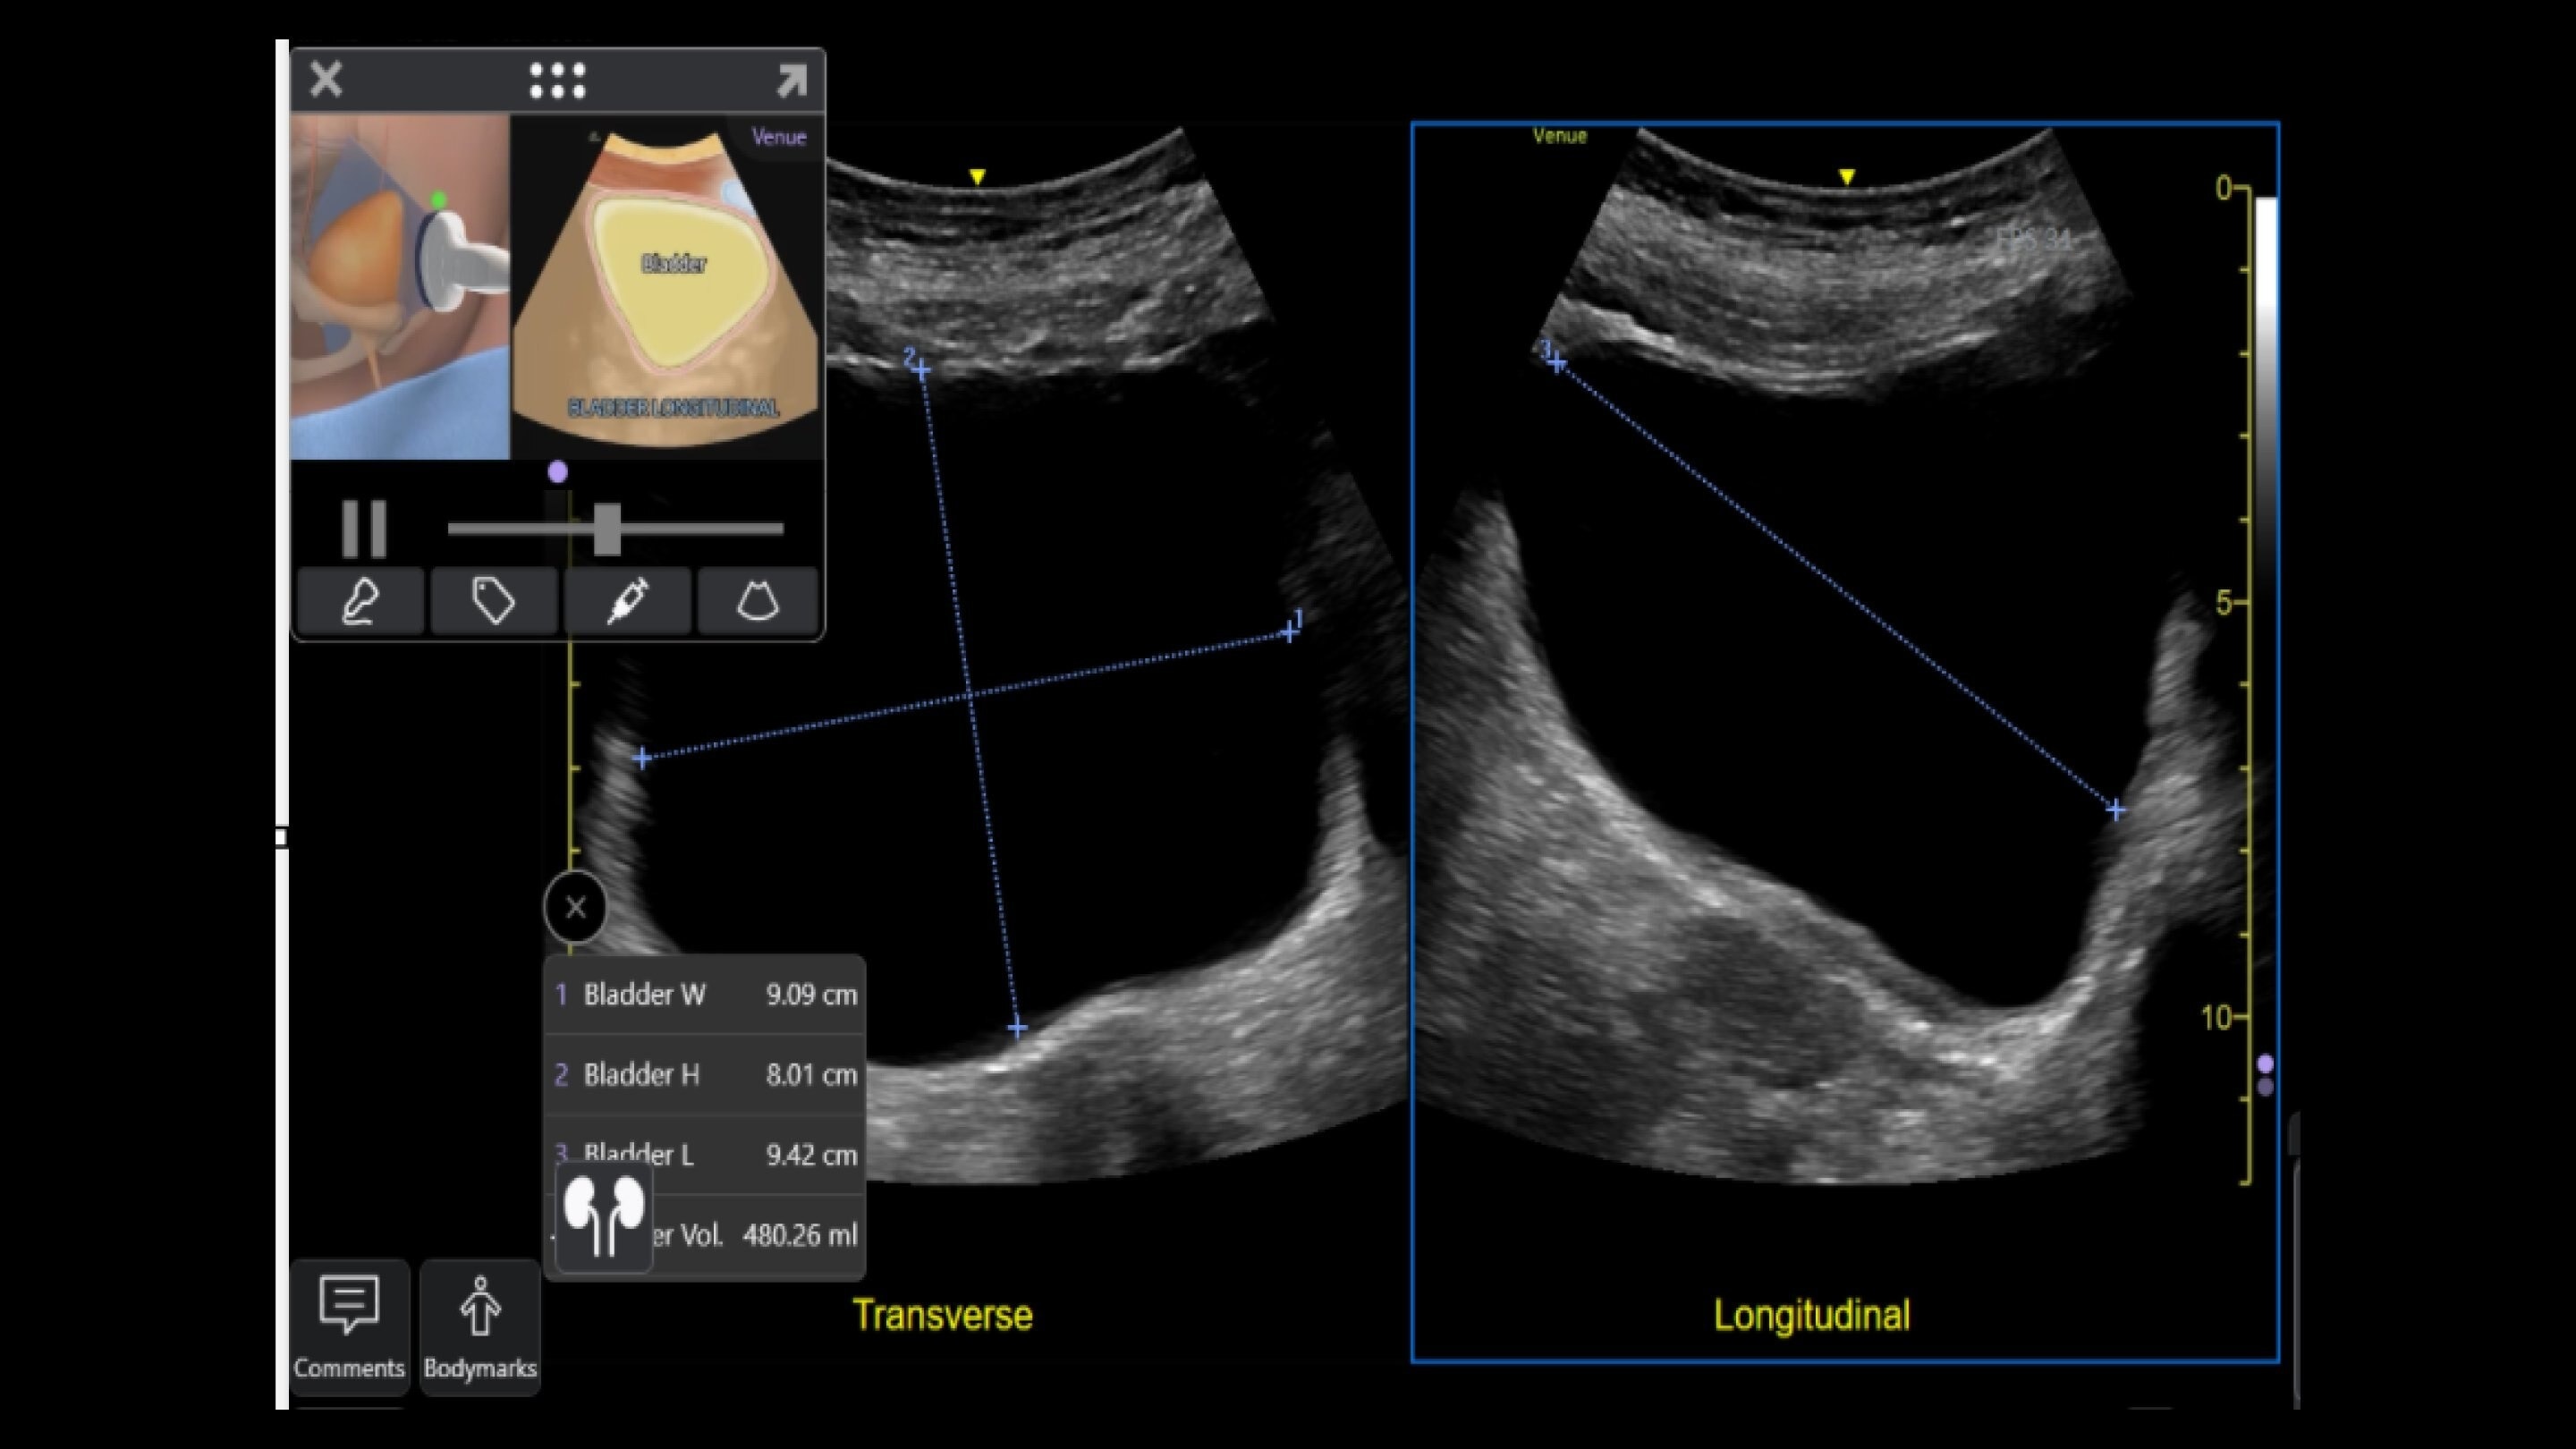

Venue Sprint™ gives you the uncompromised image quality and smart workflow of Venue™ family systems along with the freedom and maximum portability of wireless probes. This all-in-one, entry-level solution combines wireless connectivity with a small, streamlined console. It features Venue family software, to give you access to the AI tools you need, to simplify advanced exams whenever and wherever care is needed.

With the portability and mobility to go anywhere, you can get ahead with Venue Sprint. Take handheld ultrasound to different clinical spaces, sync up and be ready to go. Venue Sprint supports a wide range of environments including:

Enables on-the-spot visual confirmation, aiding the team in decision-making and collaboration on complex cases.